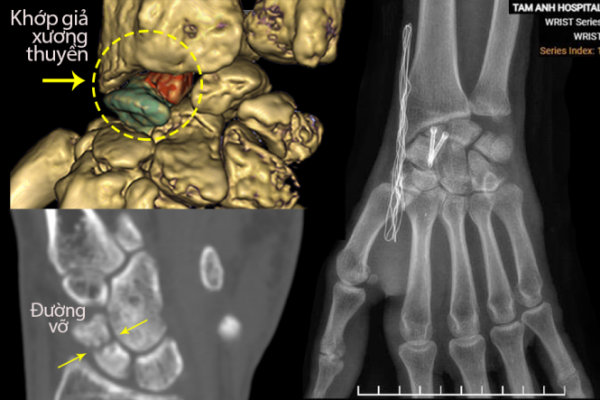

Đau cổ tay do khớp giả sau gãy xương: Nguyên nhân và điều trị

Tai nạn lao động cách đây 8 năm tại Malaysia đã khiến anh Tuấn bị một thùng phuy nặng rơi trúng tay phải, gây rạn xương thuyền. Đây là loại xương nhỏ, dẹt, đóng vai trò quan trọng trong việc ổn định khớp cổ tay, giúp cổ tay linh hoạt khi gập, duỗi và xoay….